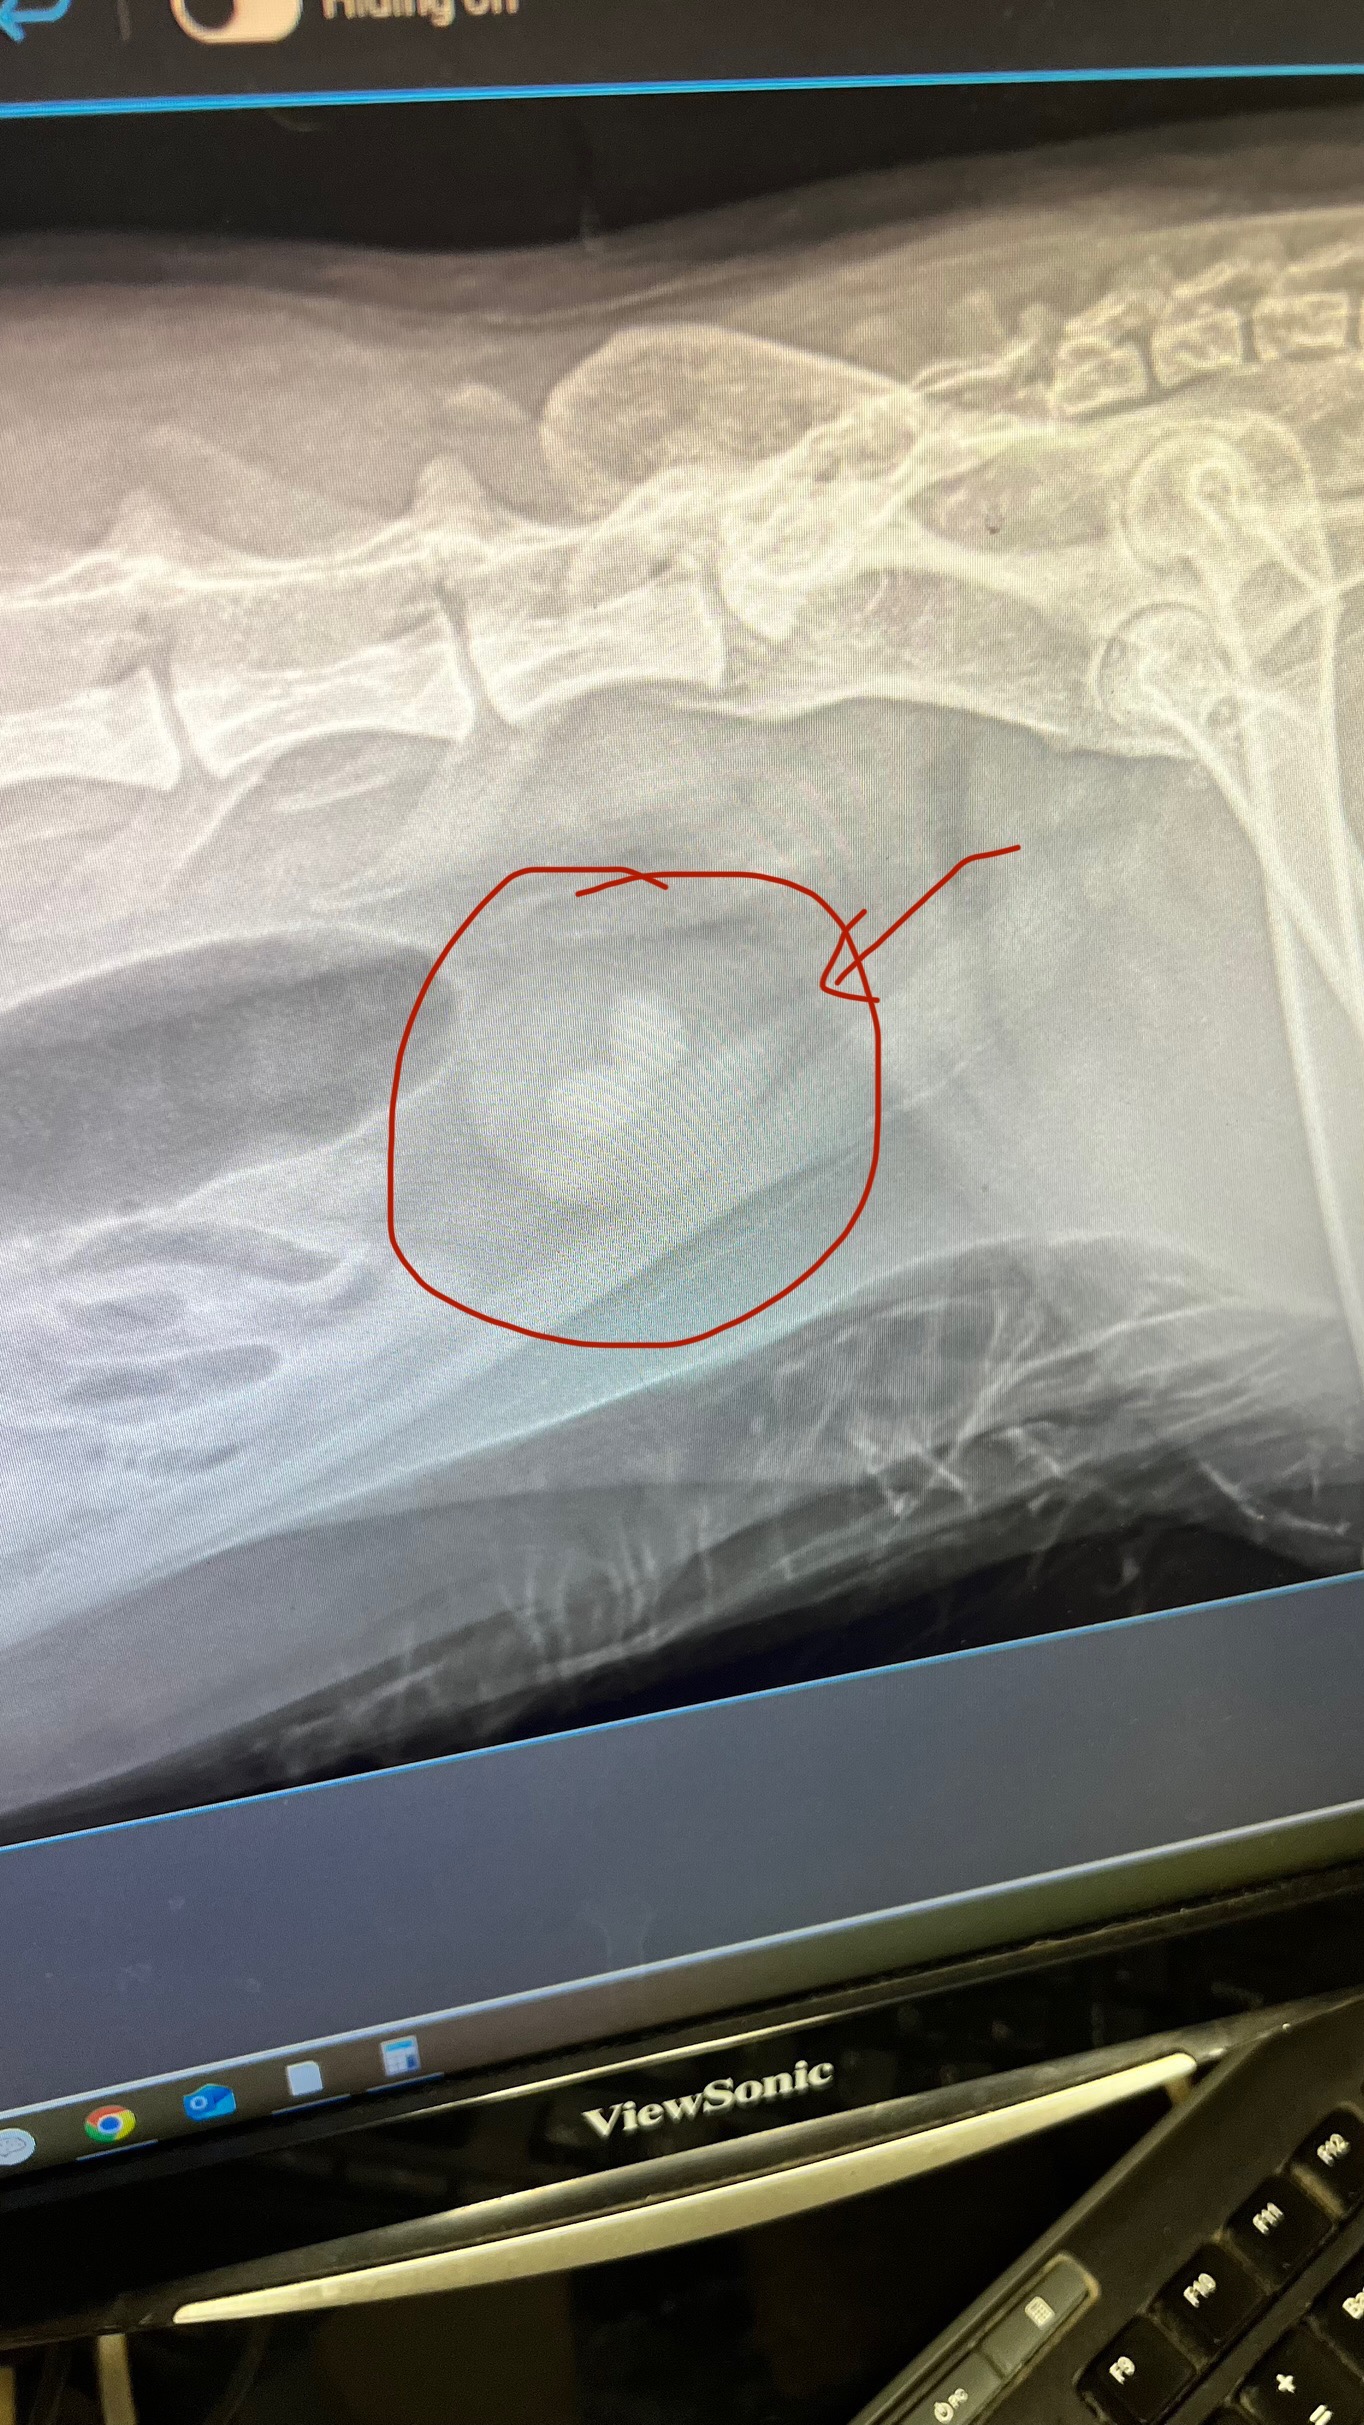

Hey y'all, it's Ernie. I really need your help for Ziggy's surgery to remove two kidney stones that are really big. The veterinarian thinks he wouldn't be able to pass them before he declines. He's 9 years old and I've had him since he was 3 months old. I saved his life by finding him face flat on the ground in my backyard and have since taken him in as my child, Ziggy Lara. Any help would be greatly appreciated. Thank you.